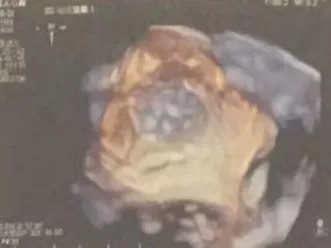

DSA肝位造影,心耳形态为鸡翅型;

ICE下心耳开口略低于左上肺静脉开口,属于低位心耳;